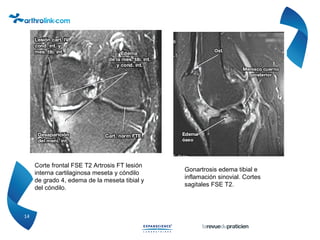

Ruptura de las articulaciones de

rotación. En RM en T2.

Osteonecrosis del cóndilo femoral

externa, RM secuencia T1, corte

frontal.